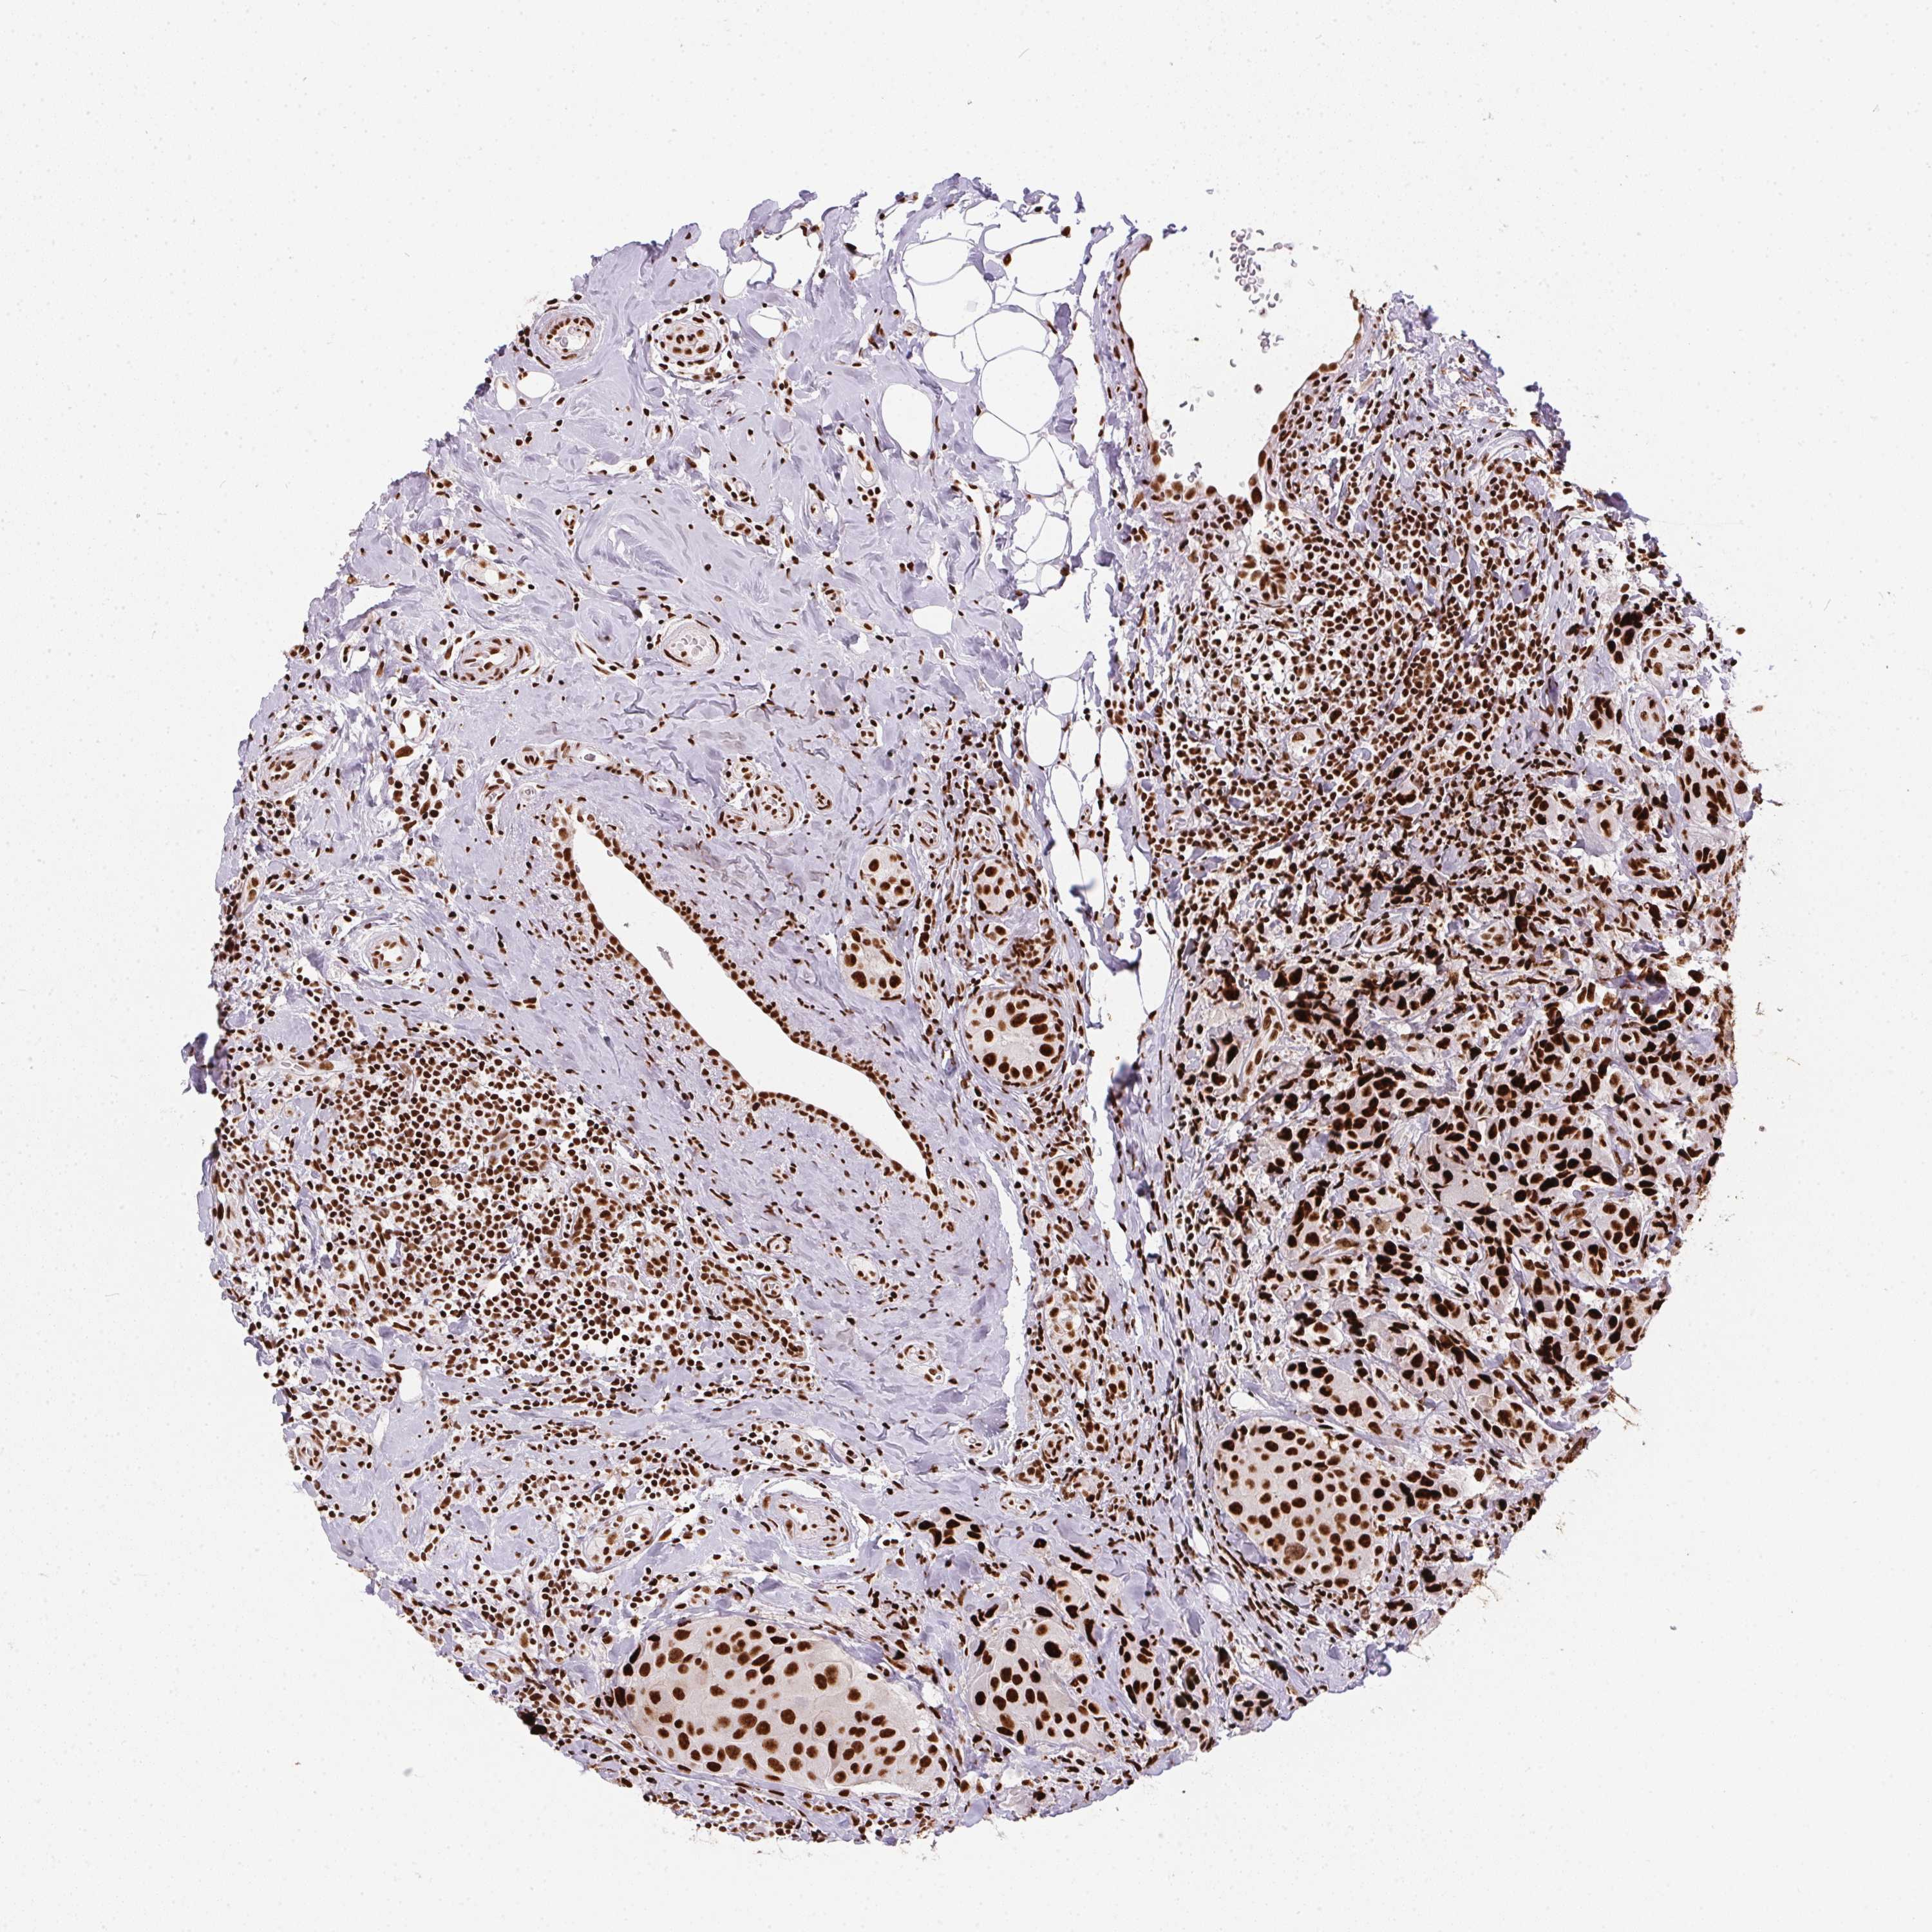

CANCER BREAST CANCER Show tissue menu

Breast cancer

Human cancer